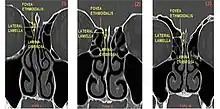

From left to right, Keros type I, II, and III.

The Keros classification is a method of classifying the depth of the olfactory fossa.

The depth of the olfactory fossa is determined by the height of the lateral lamella of the cribriform plate. Keros in 1962, classified the depth into three categories.[3]

• type 1: has a depth of 1–3 mm (26.3% of population)

• type 2: has a depth of 4–7 mm (73.3% of population)

• type 3: has a depth of 8–16 mm (0.5% of population)

• type 4: has asymmetric depths (described by Stammberger)